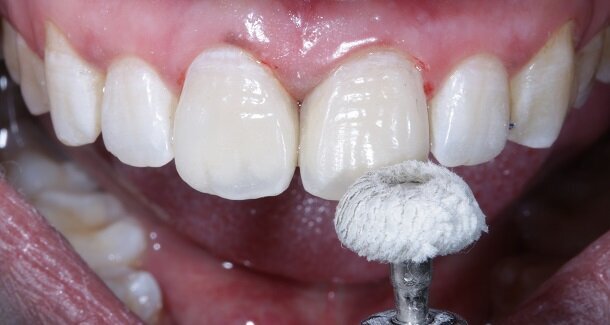

Fig 18 - Pre-polishing was done using a 3M soflex white spiral under pressure on a contra-angled handpiece.

Fig 19 and 20 - Polishing was done by using 3M soflex beige and purple spirals in sequence.

Fig 21 - Final polishing for high gloss was done using a dry Buff (unidirectional, high speed and feather touch).